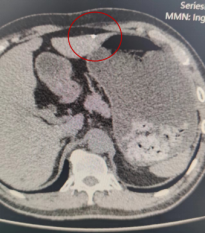

△唐先生腹部CT情况

经过CT检查,医生发现唐大哥右上腹壁有金属异物存留,异物头端经过皮下组织,穿入肝左叶。检查报告出来后,普外科程明主任考虑到患者病情紧急,当天下午3点半便紧急安排手术。在手术方式的选择上如果行开腹探查,无疑会留下巨大伤口,经慎重考虑,决定为唐先生行“单孔腹腔镜探查+肝内异物取出+肝破裂清创修补术”。